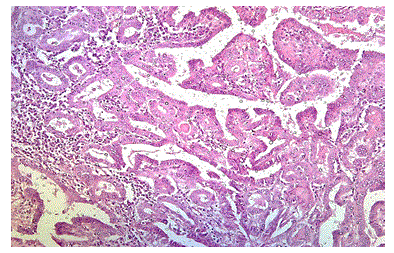

Illustrations

Figure 3: Photomicrograph Showing Papillary Thyroid Carcinoma with Strong and Diffuse Cytoplasm Positivity for BRAF V600E (case no: 21)

Figure 4: Photomicrograph Showing Papillary Thyroid Carcinoma, H&E, 100X (case no: 3)